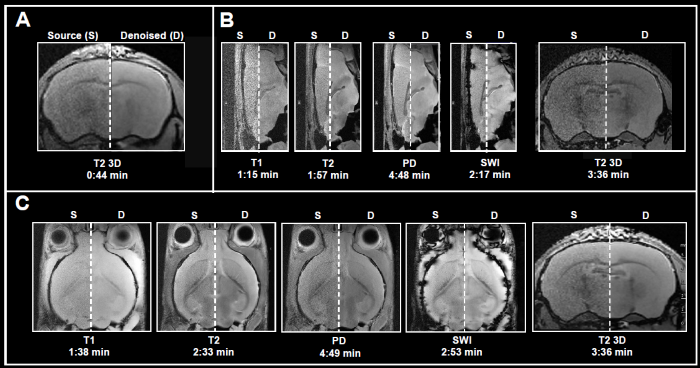

Obtaining MRI data is a slow process, and acquisition times increase alongside higher spatial resolution when extensive volumetric coverage is needed and/or multiple contrast images or quantitative data sets are gathered. Acquiring high SNR data in a reasonable amount of time is highly sought after. Here, Bruker showcases the use of Smart Noise Reduction to denoise fast structural brain scans.

Fig. 4 displays examples of ex vivo brain scans of different contrasts and orientations gathered in less than 5 minutes. The data was obtained from 3, 7, and 9.4 Tesla tools. To achieve the desired short acquisition time, standard protocols prepared for each system were improved by removing averaging, as seen in Fig. 4A-C.

This resulted in 7-15 times faster acquisition times compared to the original protocols. Yet, given the chosen resolution, no averaging resulted in noisy images. Reconstructing the obtained data with the denoising algorithm successfully removed noise from images and delivered high-quality images.

Figure 4. Examples of fast brain scans. Ex vivo data of a fixed mouse head acquired with different image contrasts, geometries and orientations. Data were acquired at A) 3 Tesla, B) 7 Tesla, and C) 9.4 Tesla. Images were reconstructed with no denoising (Source) and with a network Strong and applying 50% pre-denoising and a denoising level of 70% (Denoised). Image Credit: Bruker BioSpin Group

In Fig. 6, axial T2-weighted TurboRARE images of a fixed mouse head obtained at various field strengths are contrasted. Images were obtained via a fixed field-of-view of 20 x 20 mm2, with 0.8 mm (3 Tesla) and 0.7 mm (7 and 9.4 Tesla) thick slices and with diverse matrix sizes to generate images with various spatial resolutions.

Of particular note, the matrix sizes were made larger by up to a factor of 1.8, 2.6, and 3.1 (vs a matrix size of 256 of the reference protocols) for images obtained at 3, 7, and 9.4 Tesla, respectively. These resolution increases lead to a concomitant loss in SNR for each image. Loss in SNR can be made up for by utilizing averaging and thus additional data was obtained with four averages.

Comparing non-denoised averaged images with single averaged images showed that denoising reduces increased image noise at elevated resolutions and results in images of similar quality to those obtained through averaging.

Improvements in image quality by denoising are more significant with data obtained at 3 Tesla, where heightening the resolution generates images that are more difficult to understand, compared to data obtained at 7 and 9.4 Tesla, where SNR is innately higher.

In any case, images obtained at 7 and 9.4 Tesla are significantly helped by denoising during reconstruction, as the intrinsically elevated SNR of these images can be used for choosing smaller voxel dimensions. Thus, denoising enables researchers to choose higher resolutions within a given unit of time, stemming from a reduced need for averaging. This can also be practical when averaging might be undesirable or impractical.